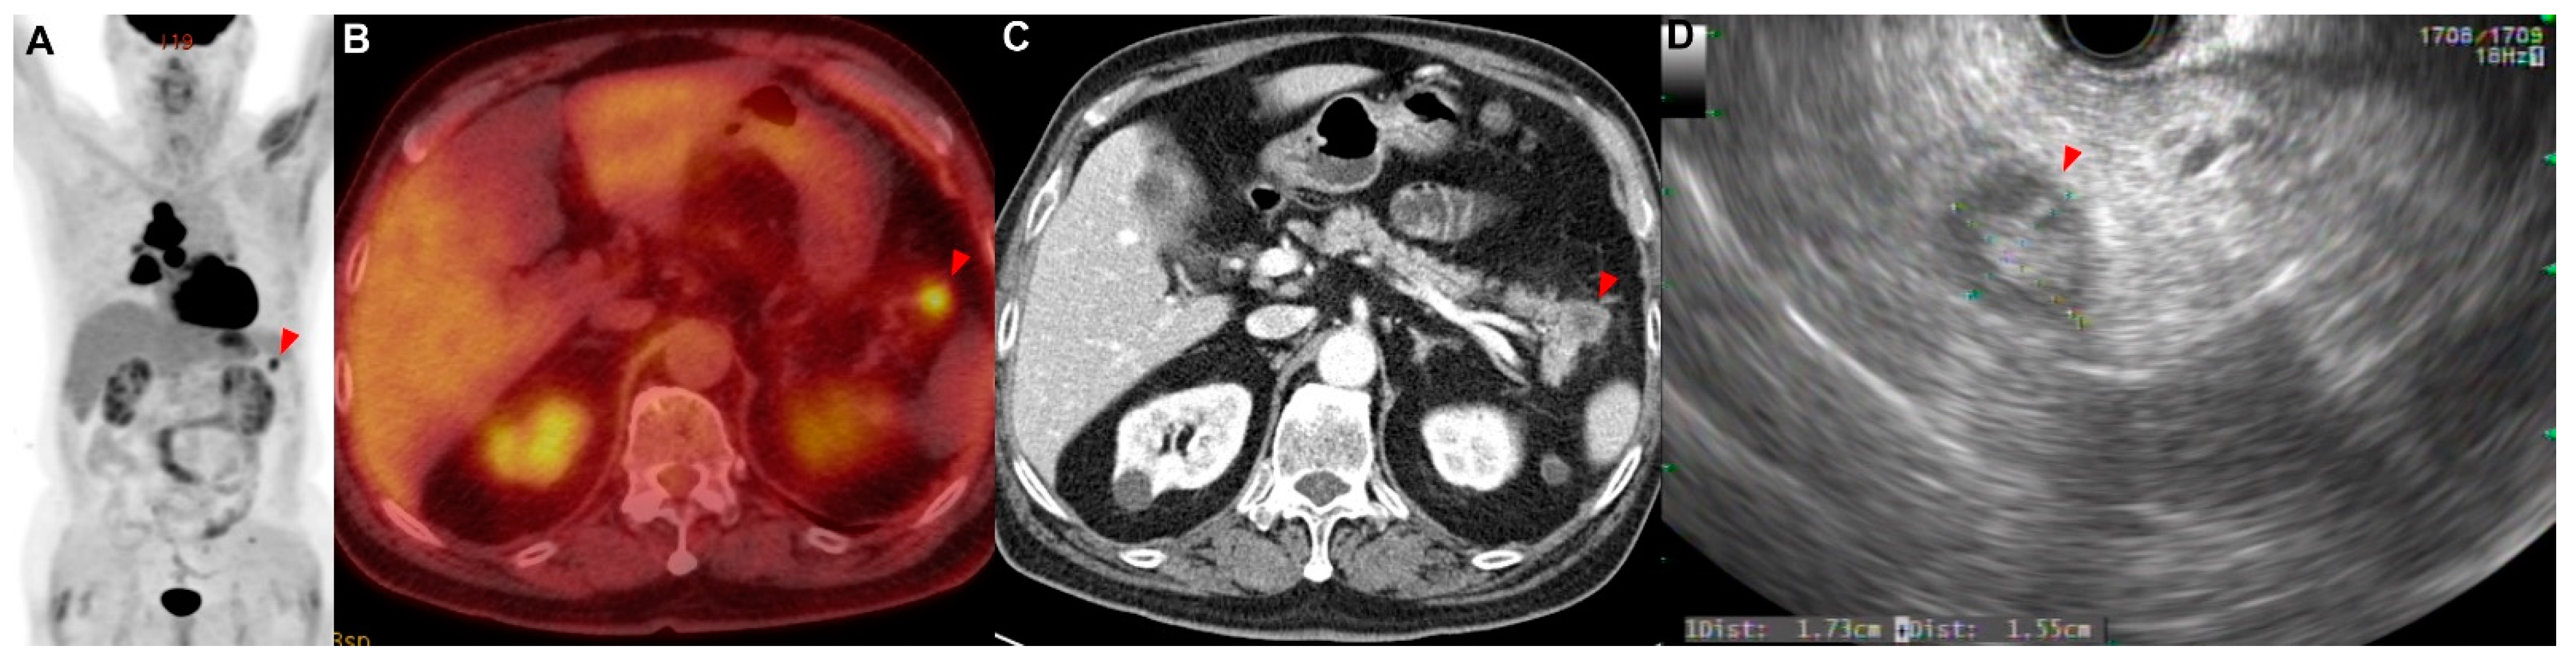

A 77-year-old man with a medical history of diabetes mellitus was referred for an abnormal chest radiograph, which was taken at a public health clinic. He had a history of 57 pack years of smoking. He stated that he did not take any medications or have any illnesses, including cardiovascular, allergic, rheumatic, or respiratory conditions. A contrast-enhanced CT scan of the chest showed a lung mass invading a lobar bronchus of the left upper lobe. A bronchoscopic biopsy was performed and squamous cell carcinoma was diagnosed. If there was no metastasis, the tumor was considered stage IIIC as T4N3. There was no suspicious finding of distant metastasis except for a hypermetabolic lesion (SUVmax = 13.42) of the bilateral lobes of the thyroid gland in PET/CT (Figure 2A,B). FNA and cytology were performed on the lesion of the left thyroid gland (Figure 2C,D), and metastasis of squamous cell carcinoma was confirmed (Figure A1B). This patient was treated with six courses of platinum-based chemotherapy (gemcitabine and cisplatin) for stage IV squamous cell carcinoma.

Figure 2. Patient 2: a 77-year-old man diagnosed with squamous cell carcinoma of the lung with metastases in the thyroid. (A,B) PET/CT showed metastatic lesions (red arrowhead) in the bilateral lobes of the thyroid. (C,D) Metastatic lesions were observed in the (C) left and (D) right thyroid.